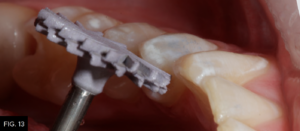

When placing composite materials using the above-described technique, very little finishing should be required except at the marginal areas. Rubber polishing abrasives (A.S.A.P. Polishers, Clinician’s Choice) are used to further polish the adjusted areas. (FIG. 13)

An A.S.A.P. Pre-polisher (A.S.A.P. All Surface Access Polishers, Clinician’s Choice) is used followed by an A.S.A.P. Final High Shine Polisher to impart a high luster surface to the composite material.